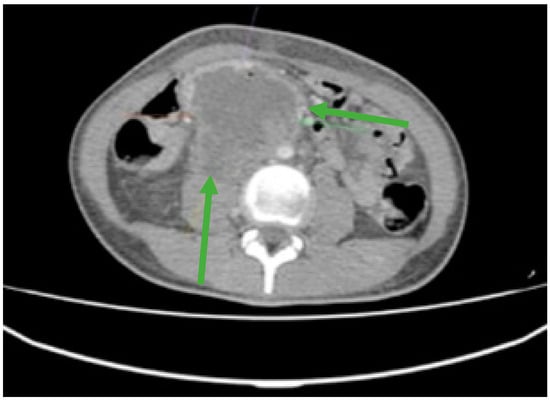

In this report, we will discuss the case of an 18-year-old male patient who presented with a complex set of symptoms, including melena, hematemesis, pallor, and severe fatigue. The patient’s symptoms were primarily attributed to gastrointestinal hemorrhage, specifically originating from a retroduodenal mass (Figure 1), which represented the primary cause for his urgent hospital admission. While testicular cancer can present with metastatic manifestations in around 10–12 percent of patients, it is still a very unusual presentation and difficult to be assessed by the clinicians.

Figure 1.

Contrast-enhanced computed tomography (CT) revealed an irregular, slightly rounded retroperitoneal abdominal mass measuring 70 × 98 × 66 mm (green arrows).

Furthermore, laboratory investigations revealed severe anemia with a hemoglobin level as low as 4.2 g/dL. To gain a comprehensive understanding of the extent of the disease and its impact on the patient’s overall health, an extensive evaluation was conducted. This assessment included Endoscopic Retrograde Cholangiopancreatography (ERCP) and whole-body computed tomography (CT). These diagnostic tests collectively confirmed the presence of an extended retroperitoneal mass (Figure 1), which had invaded the duodenum, thus underscoring the severity and complexity of the patient’s condition.

During the maintenance therapy with oral etoposide, the plasma beta HCG was highly increased (6228 mIU/mL), so we decided to start third line chemotherapy with GOP (gemcitabine 800 mg/sqm day 1 and 8, paclitaxel 80 mg/sqm day 1 and 8, oxaliplatin 130 mg day 1, q3w). After five cycles, we observed a new biological and imagistic progression (Figure 3 and Figure 4) in the size and number of the liver and lung metastases that appeared.

Figure 4.

CT scan showing liver metastases in numerical and dimensional progression (green arrows).